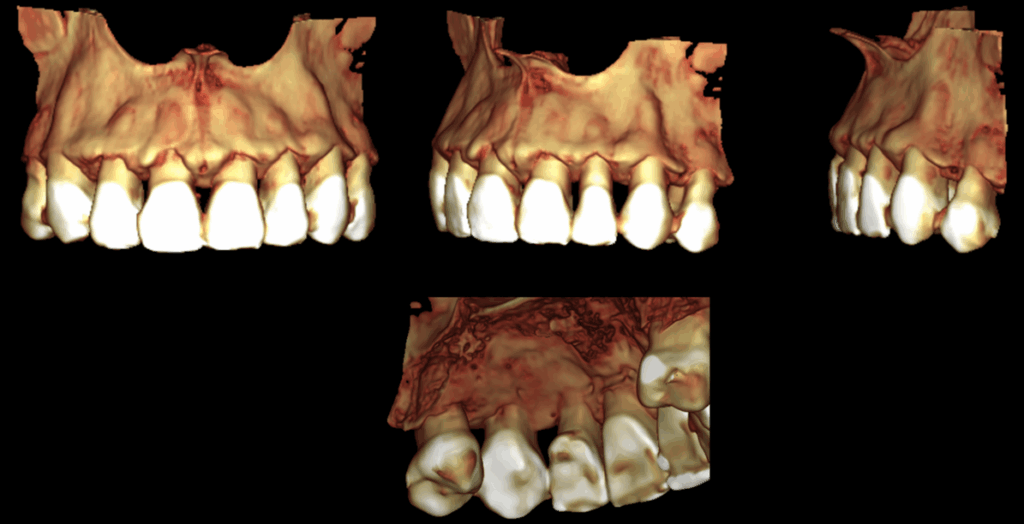

RECONSTRUCCIÓN 3D

En la tomografía computarizada de haz cónico se identifica en la pieza 23 una imagen isodensa que compromete las paredes radiculares mesial, distal y palatina a nivel del tercio cervical, en estrecha proximidad con el conducto radicular. Asimismo, se observa un ensanchamiento del espacio del ligamento periodontal adyacente.

- Reabsorción cervical externa en pieza 23.